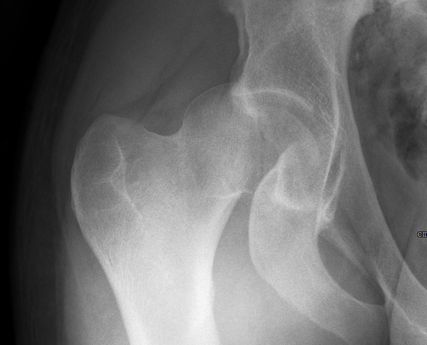

Abb. 2: Ergänzend zur anterior-posterioren Aufnahme bedarf es einer axialen Röntgenaufnahme. Deutlich sichtbar ist das dislozierte Fragment des Femurkopfes rechts

Neben der klinischen Erstuntersuchung und Anamnese umfasst die Diagnostik die konventionelle native Röntgendiagnostik des verletzten Hüftgelenkes mit Standardaufnahmen im a.-p. und axialen Strahlengang (Abb. 1, 2) sowie gegebenenfalls die Anfertigung von Ala- und Obturatoraufnahmen. Obligatorisch empfehlen wir die Anfertigung eines Hüftübersichtsröntgens und gegebenenfalls, sofern möglich, auch eine Faux-Profil-Aufnahme. Zur präoperativen Planung und zur Beurteilung des Repositionsergebnisses ist der Goldstandard die Computertomografie (Abb. 3) mit Anfertigung einer 3D-Rekonstruktion. Im Rahmen der Notfalldiagnostik spielt die Magnetresonanz keine wesentliche Rolle. Im Hinblick auf die Diagnostik sekundär auftretender Komplikationen ist jedoch die Bedeutung des MRT unumstritten.